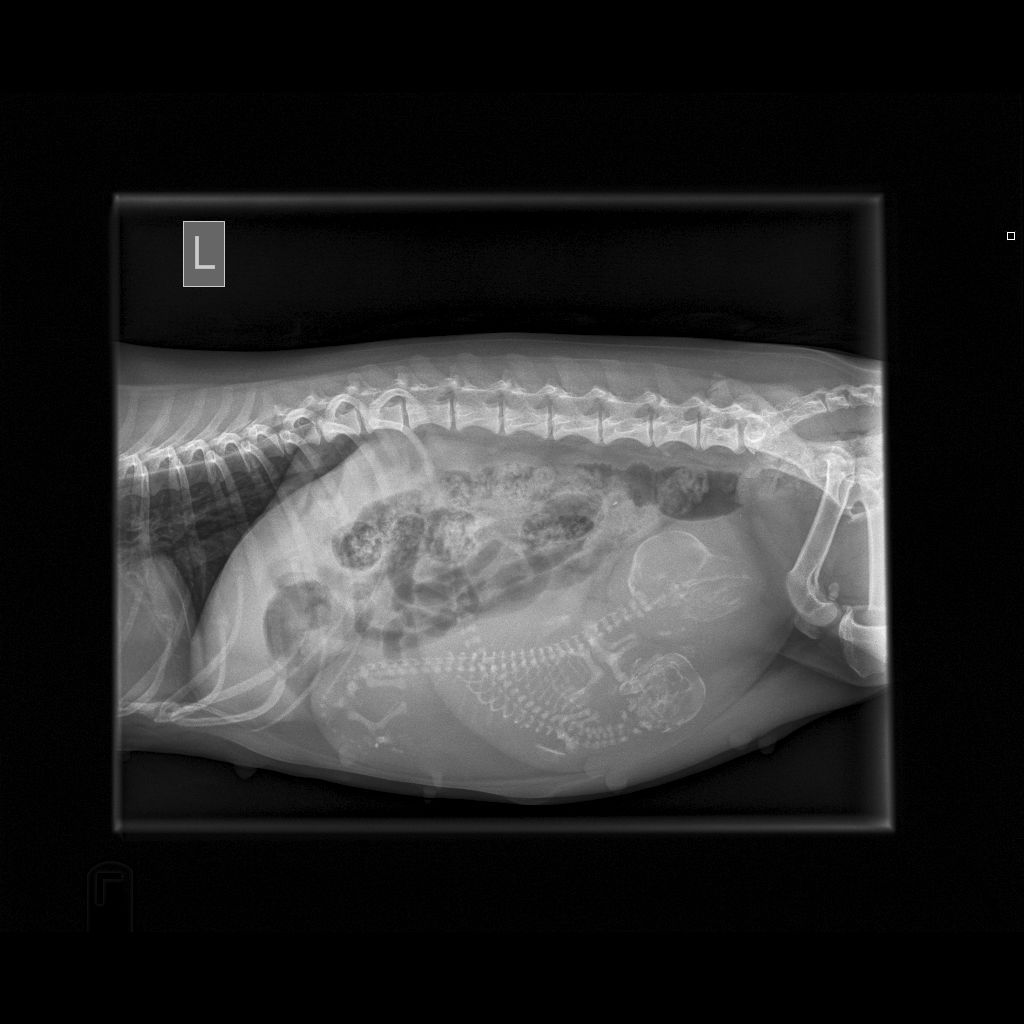

August 29, 2017 - Xray done - Gem has 2 puppies in there. She is a small girl so hopefully all goes well. Won't be long now! See xray below.